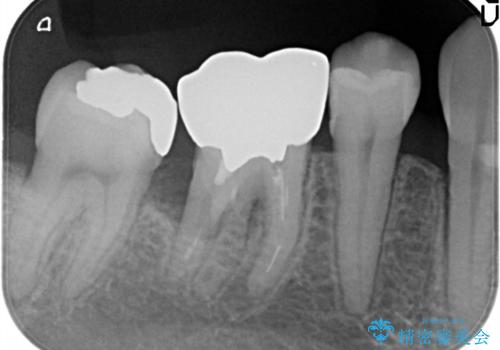

- 奥歯が痛いことを主訴に来院されました。

遠心根に歯根破折を認め、保存不可と判断しブリッジにて欠損補綴を行なっております。

歯根の縦方向への破折は保存不可となることが多いです。